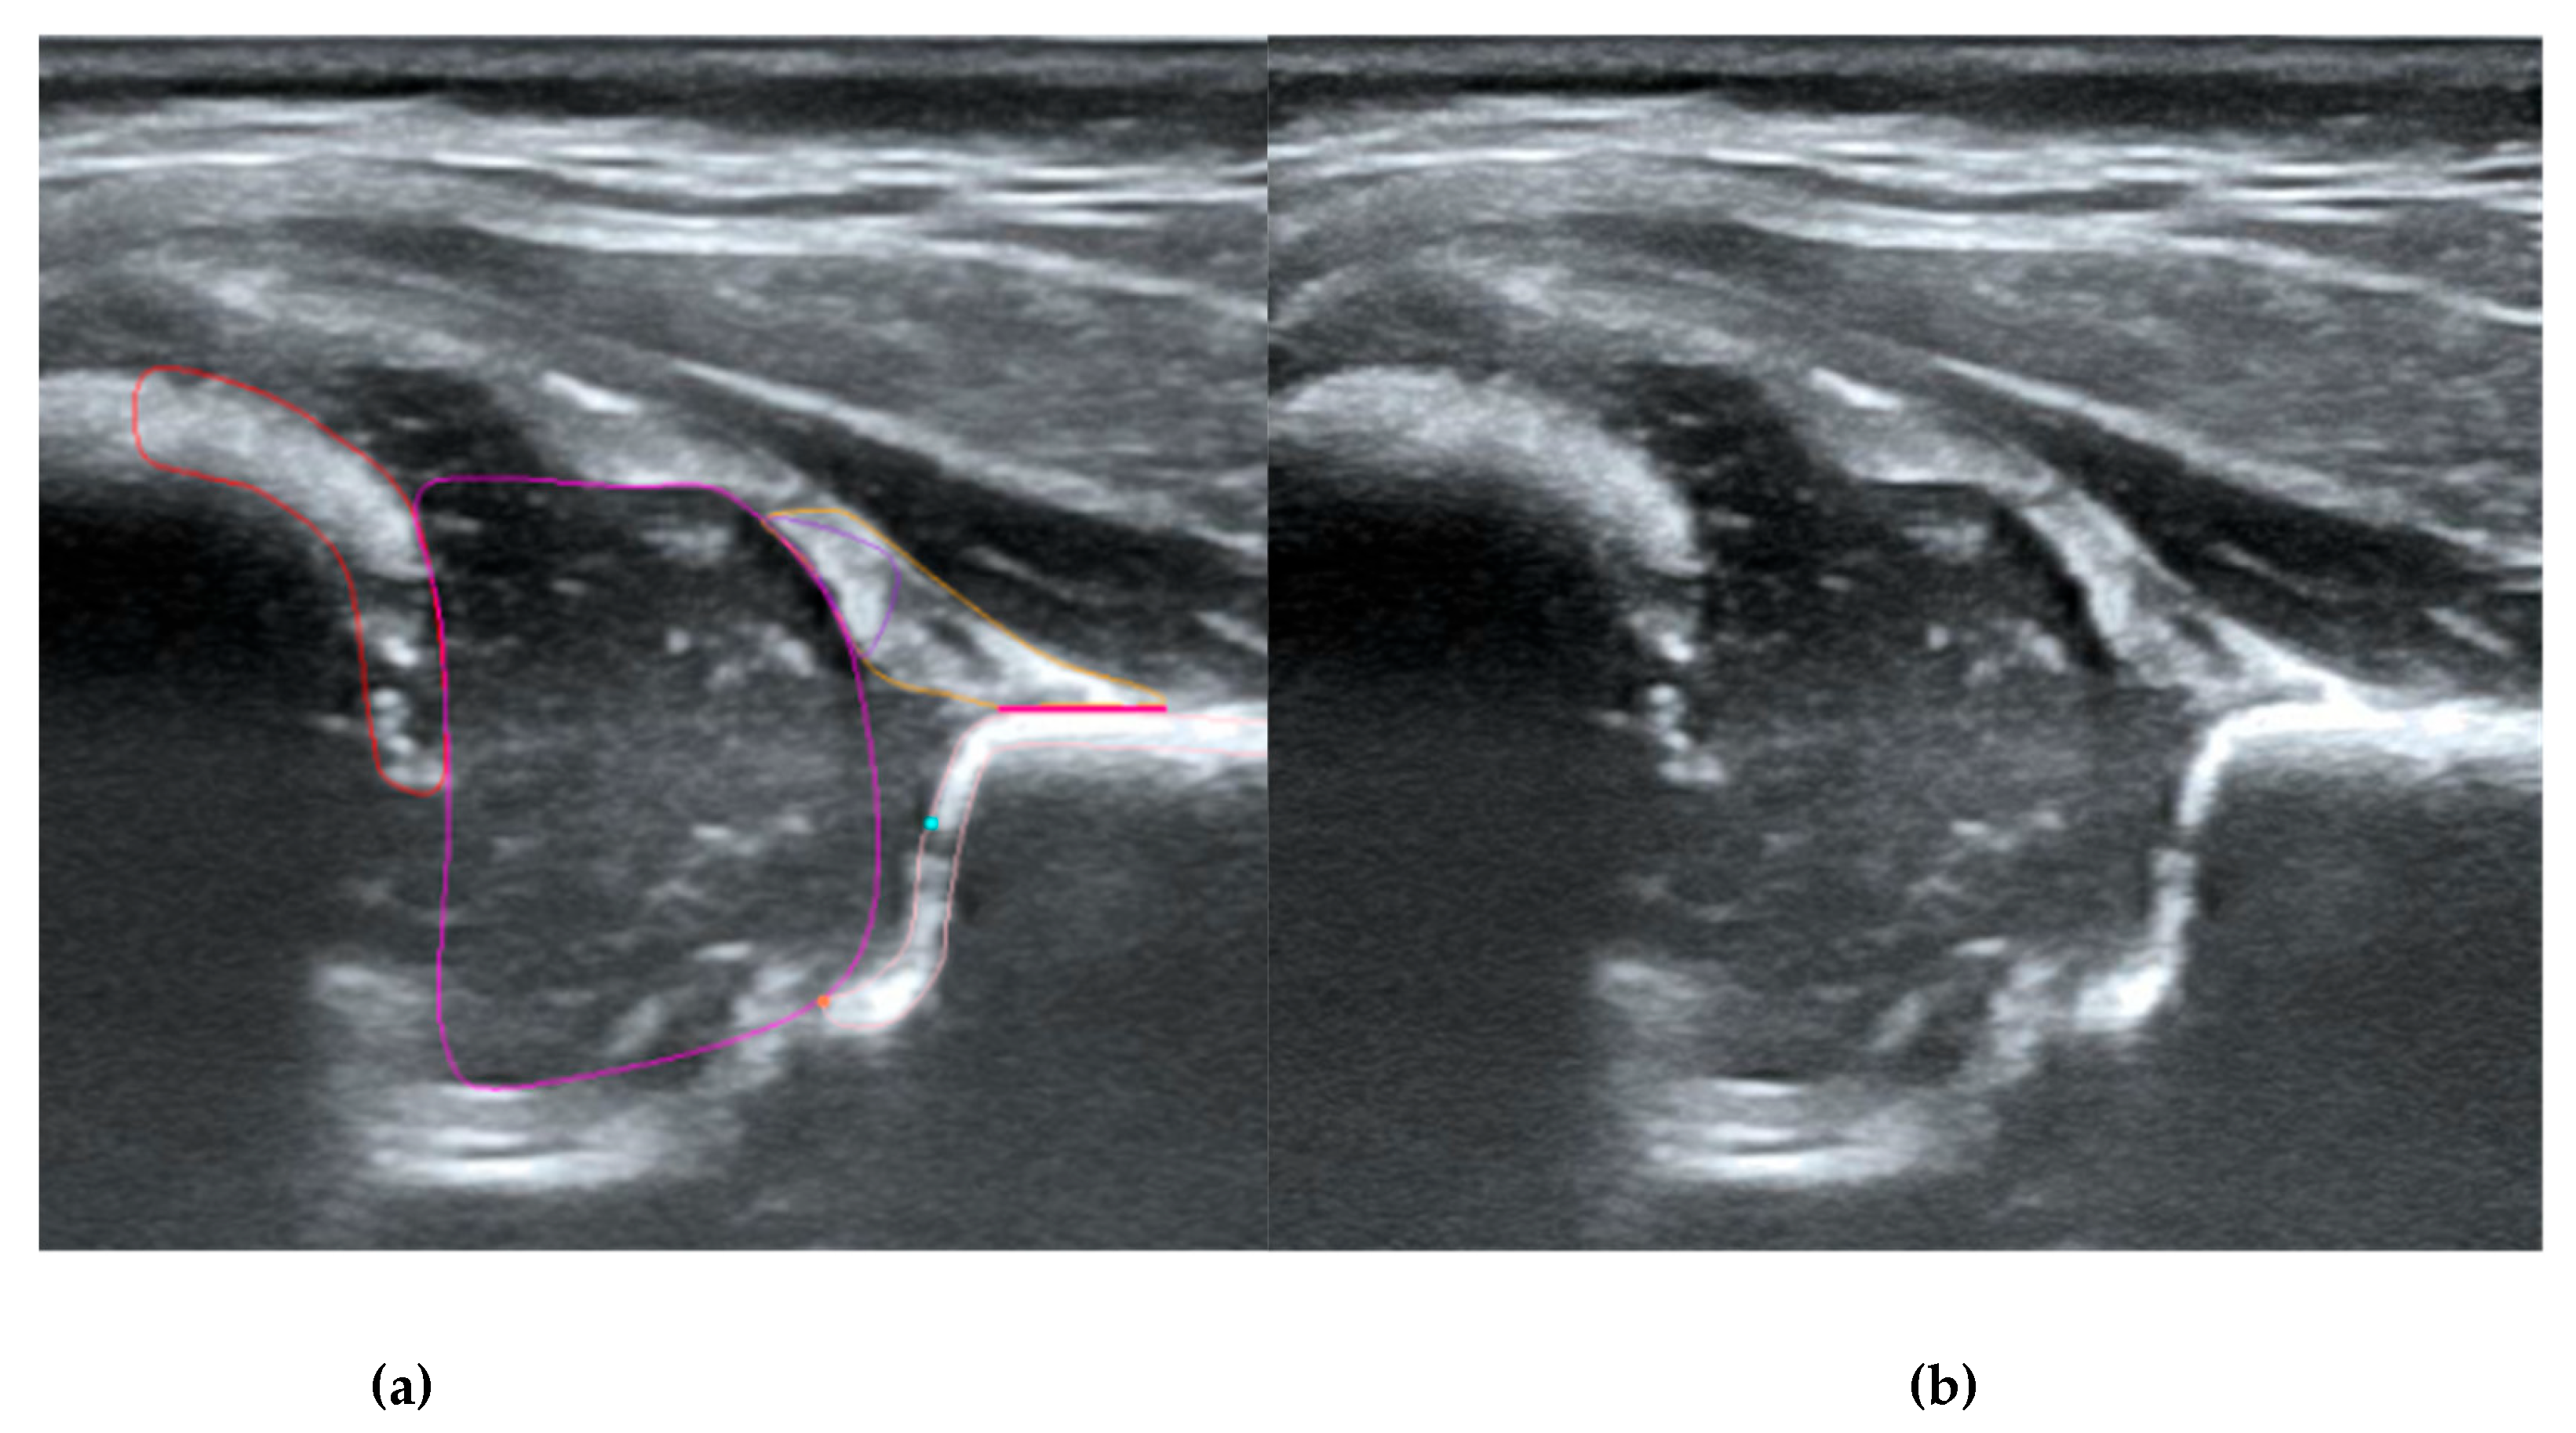

Figure 1. Ultrasound image of the hip in Graf standard plane (a) and labeling of anatomical structures (b). The labeled diagram (b) includes 5 anatomical structures, i.e., chondro-osseous border (red), femoral head (purple), cartilaginous roof (yellow), bony roof (beige), and labrum (light purple). Other landmarks include lower limb (orange), bony rim (light blue), and baseline (pink).

The structures were annotated by three independent orthopedic surgeons trained in the Graf method who had participated in a Graf-accredited course. The contours of the anatomical structures in the US images were marked using points along the edges of the target anatomy by dedicated software on selected frames. In the annotation process, a maximum of 25 frames from each video were selected by the reporting physician as the best. Annotating physicians selected structures for marking from a drop-down list among the objects on Checklists I and II according to Prof. Graf, necessary for the assessment of hip joints for DDH (Figure 1). Frames were selected for annotation only when it was possible to mark 5 or more objects. Furthermore, at least one selected frame in each video was classified as diagnostic, according to the Graf methodology (standard plane)[14].